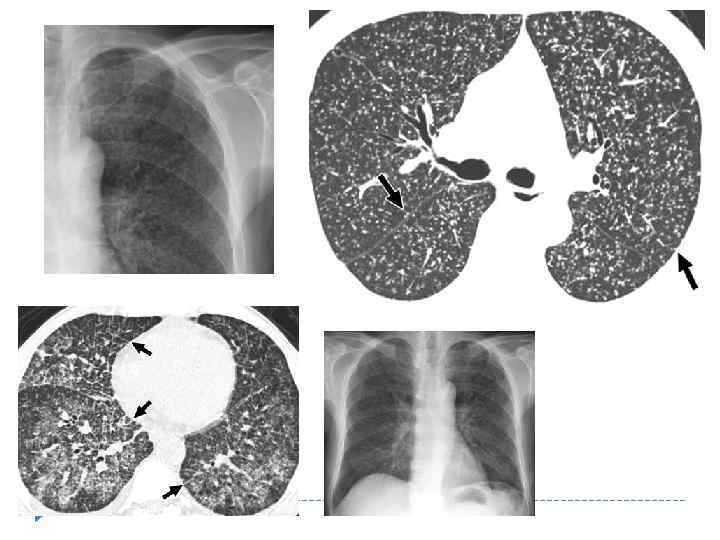

Рентгенологические признаки МТЛ Основной рентгенологический синдром: очаги и очаговая диссеминация в лёгочном поле Мелкоочаговый до 3 мм. Часто рентгенологические изменения появляются, только на 7 -10 сутки, после начала клинических проявлений

Рентгенологические признаки МТЛ Основной рентгенологический синдром: очаги и очаговая диссеминация в лёгочном поле Мелкоочаговый до 3 мм. Часто рентгенологические изменения появляются, только на 7 -10 сутки, после начала клинических проявлений

Рентгенологические признаки МТЛ Двухсторонняя симметричная мелкоочаговая диссеминация мономорфные очаги Форма очагов округлая Контуры относительно четкие Структура однородная Малая интенсивность очагов диффузное понижение прозрачности лёгочных полей нечёткость (смазанности) лёгочного рисунка Полости деструкции и эмфизема легких отсутствуют.

Рентгенологические признаки МТЛ Двухсторонняя симметричная мелкоочаговая диссеминация мономорфные очаги Форма очагов округлая Контуры относительно четкие Структура однородная Малая интенсивность очагов диффузное понижение прозрачности лёгочных полей нечёткость (смазанности) лёгочного рисунка Полости деструкции и эмфизема легких отсутствуют.

Милиарный туберкулёз лёгких

Милиарный туберкулёз лёгких

Рентгенологические признаки МТЛ при КТ исследовании Большинство очагов располагается в легочной ткани хаотично и установить их взаимосвязь с анатомическими элементами долек легкого обычно не представляется возможным Очаговые изменения сочетаются с умеренно выраженной реакцией интерстициальных структур в виде диффузного утолщения междольковых перегородок В некоторых из них видны мелкие очаги Часть очагов располагается в кортикальной и междолевой плевре

Рентгенологические признаки МТЛ при КТ исследовании Большинство очагов располагается в легочной ткани хаотично и установить их взаимосвязь с анатомическими элементами долек легкого обычно не представляется возможным Очаговые изменения сочетаются с умеренно выраженной реакцией интерстициальных структур в виде диффузного утолщения междольковых перегородок В некоторых из них видны мелкие очаги Часть очагов располагается в кортикальной и междолевой плевре